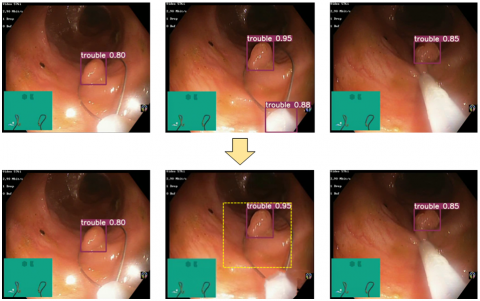

(a) Previous frame                 (b) Frame with missed detection                       (c) Next frame

Figure 2. Motion information fusion mechanism for eliminating missed object detection

When a frame with missed detection of a target occurs in a sequence group containing the same target, the algorithm fused with motion information can calculate the range where the target should appear in that frame based on the position of the target in the previous frame and the maximum movement distance of the target. This range is used as the detection box of the target. As shown in Figure 2, the target is not detected in (b). According to the detection results in (a) and (c), it can be judged that the target must exist in (b). Therefore, (b) is a frame with missed detection. According to the position in (a), the approximate position range of the target in (b) can be judged, i.e., the yellow dashed box in the figure, and it is used as the detection box of the adenoma in frame (b). It is not difficult to see from the figure that the blue dashed box is the true position of the adenoma. It can be seen that this method has a certain effect in eliminating missed detections.

In addition, this method also performs very well in eliminating false detections. The elimination of false detection situations is shown in Figure 3.

Since the prediction box given by motion information is calculated based on the target’s movement speed and represents the maximum movement range of the target, when the target appears in the previous frame, it can only appear within the predicted range in the next frame. If a target appears in a single frame but is not within or exceeds the predicted range, it proves that the target is a false detection and needs to be excluded. As shown in Figure 3, a false detection target appears at the bottom of (b), and this target does not appear in the inferred area from (a), nor does it appear in the next frame (c). Therefore, this target is a result of a false detection generated by the algorithm. It is filtered out by the algorithm during the post-processing process. It can be seen that this method can play a positive role in eliminating false detections.